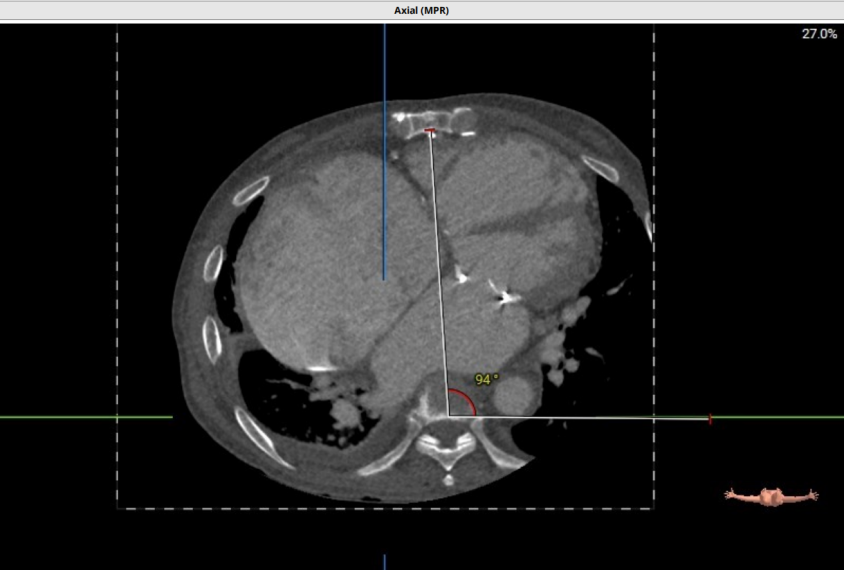

术前CT评估示:患者二尖瓣生物瓣置换术后,原生物瓣型号未知,生物瓣金属环平均内径25.9mm,外径31.5mm,瓣架高度15.9mm;

左心室和二尖瓣轴线角度:135°;

左室大小:95.3*36.5*34.2mm;

模拟27mm瓣膜植入情况:

主动脉-二尖瓣角度:102.3°;

术中建议造影角度:RAO 58°/CRA 44°;RAO 49°/CRA 62°。